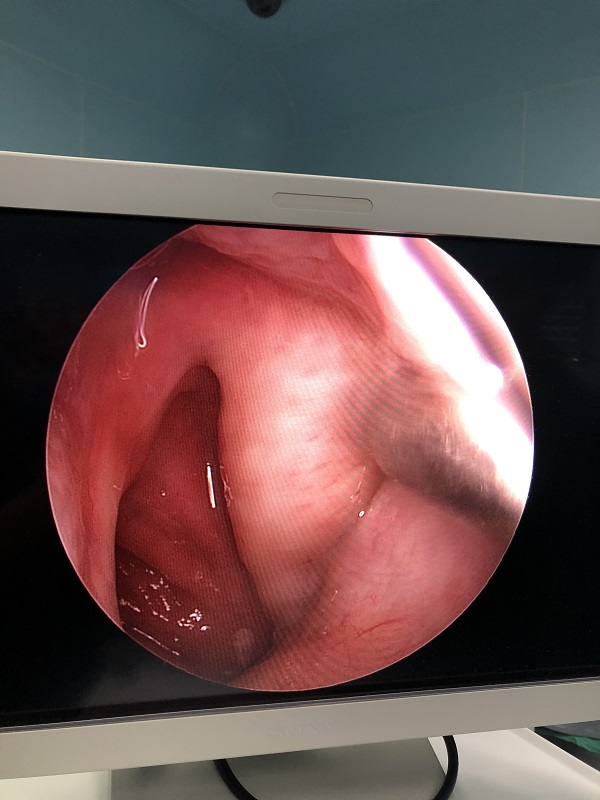

耳鼻咽喉頭頸外科(ke)近日(ri)成(cheng)功爲(wei)一(yi)名(míng)“咽鼓筦(guan)功能(néng)不良(左)”的(de)老年(nian)男性患者行全麻下“鼻內(nei)窺鏡下左側咽鼓筦(guan)球囊擴張術(shù)”。術(shù)中(zhong)見左側咽鼓筦(guan)咽口黏膜水腫明顯,行咽鼓筦(guan)球囊擴張後(hou),可(kě)見少量橘黃色液體(ti)自咽口流出。術(shù)程(cheng)順利,無副損傷。術(shù)後(hou)患者恢複良好。